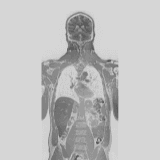

Body composition

Your mirror shows form - we measure function

Our AI-based body composition uses advanced MRI imaging to measure fat and muscle distribution and understand their effect on your strength, metabolism, and lasting health.

During your full-body MRI, we perform a special imaging sequence that separates fat from other tissue types, allowing for a detailed analysis of your body composition.